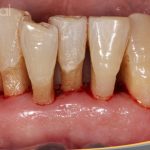

Testimonio de paciente con enfermedad periodontal avanzada- Anestesia local: Adormece solo el área alrededor de la muela.

Testimonio de paciente con enfermedad periodontal avanzada